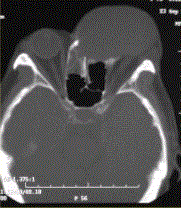

问题 患者男,60岁,头痛,前额部局部隆起。查体:前额隆起处可触及乒乓球样肿块,CT显示如下图。 鼻窦黏液囊肿的发病机制为

选项 A.窦壁黏膜下腺体轻度炎症或变态反应 B.乳牙根管感染 C.龋齿使牙髓慢性感染坏死 D.鼻窦的自然开口长期阻塞 E.发病机制不清楚 F.窦腔开口变异

答案 D